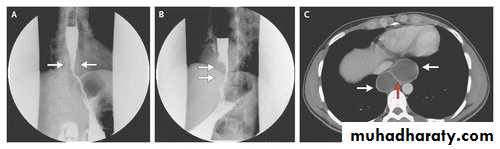

Diaphragmatic rupture

Liver herniation in right side